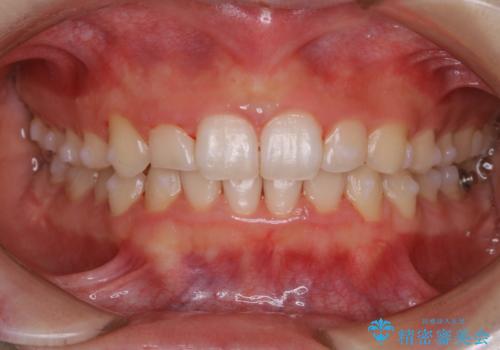

全体的にプラーク(歯垢)付着の患者様(PMTC30分コース)

- クリーニングしてほしいとのことで来院されました。

PMTC30分コースを行いました。

全体的にプラークが付着していました。